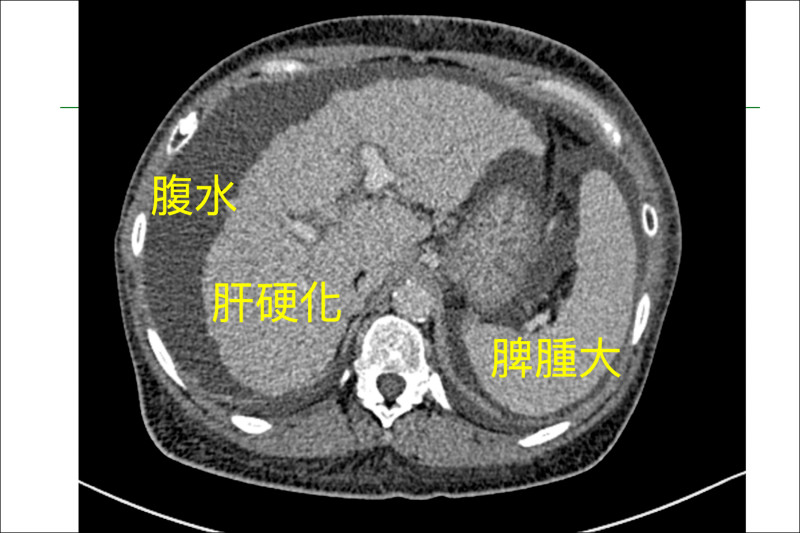

58歲帛琉籍婦人米德莉罹患原發性膽汁性膽管炎(PBC),病情惡化至最嚴重的C級肝硬化,出現腹水與門脈高壓等併發症,2年內存活率不到4成,跨海轉診來台後,在馬偕紀念醫院接受長達12小時的活體肝移植手術,由33歲兒子捐出6成肝臟,成功搶回一命,成為全台首例帛琉轉診活體肝移植個案。

馬偕外科部副主任林俊昌表示,肝硬化若未及時治療,恐出現食道靜脈曲張,一旦破裂「就像不定時炸彈」,可能瞬間致命。米德莉過去4年往返台帛兩地治療,但病情持續惡化,去年評估已達「需要換肝」,8月完成術前檢查與配對,由兒子捐肝,於8月21日進行移植手術。